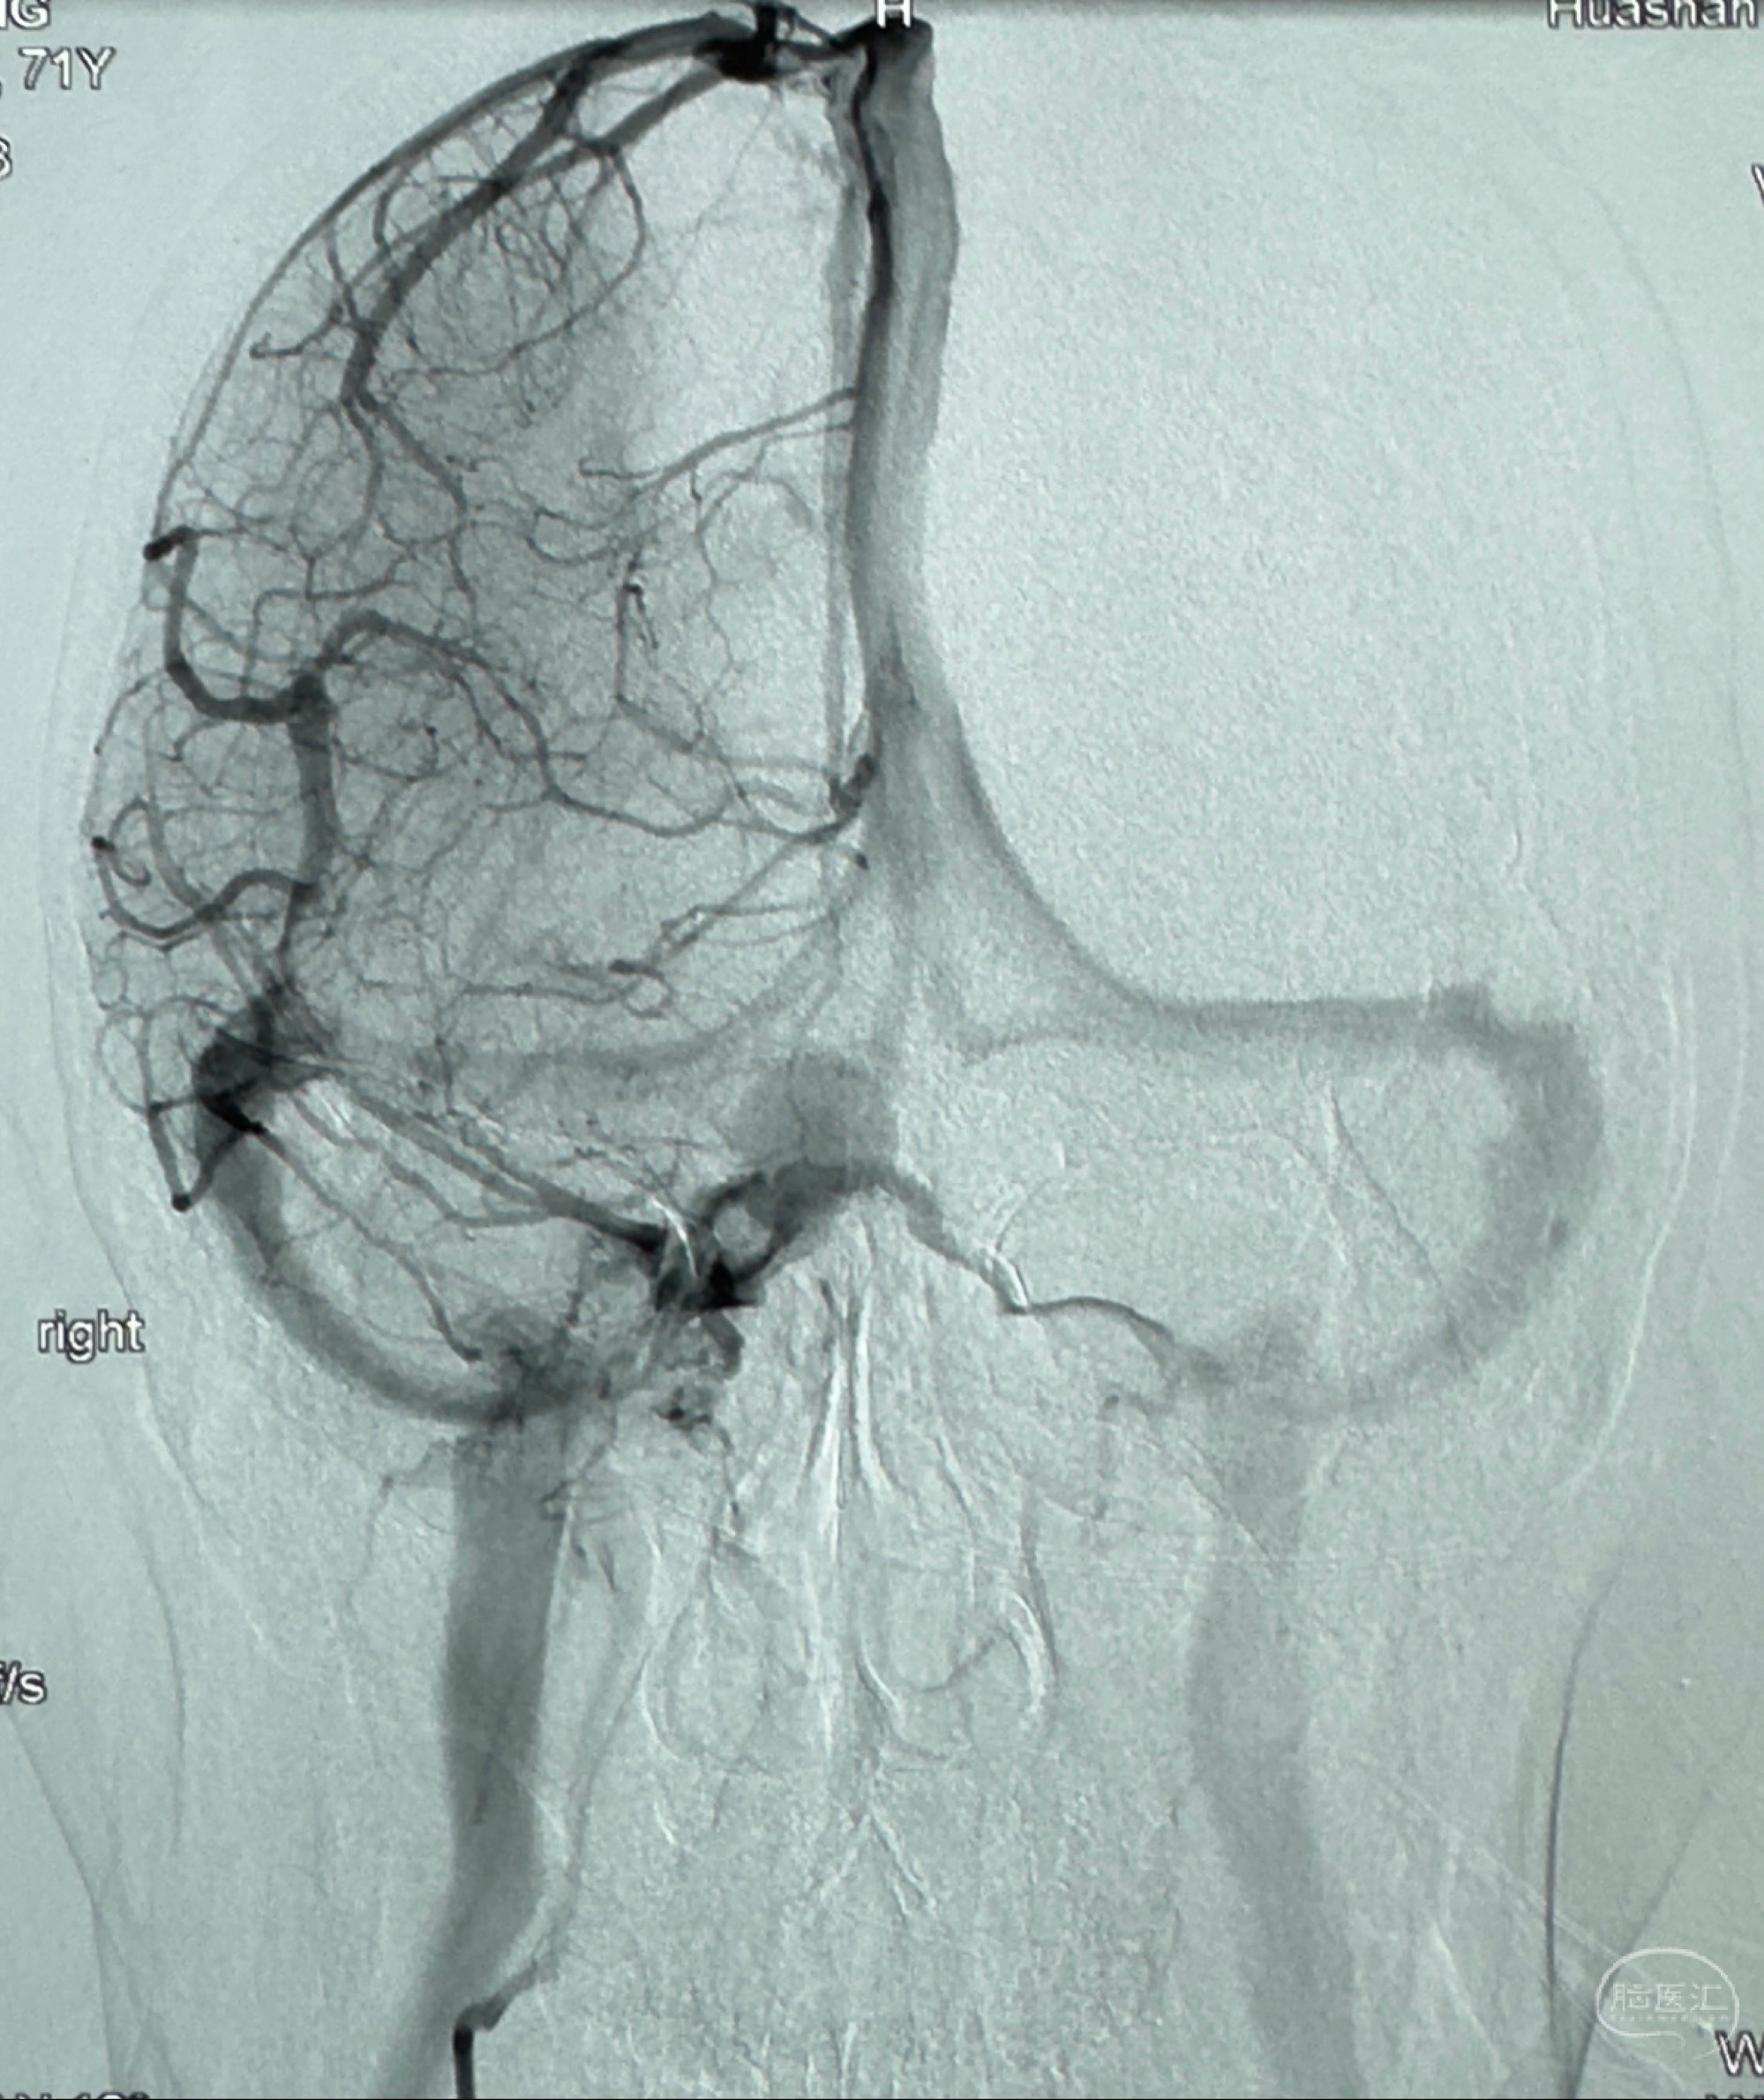

2024-01-08全麻下再行植入密网支架一枚

Tubridge 4.5-35mm

支架植入顺利,贴壁佳,支架内血流通畅,动脉瘤内血液滞留明显